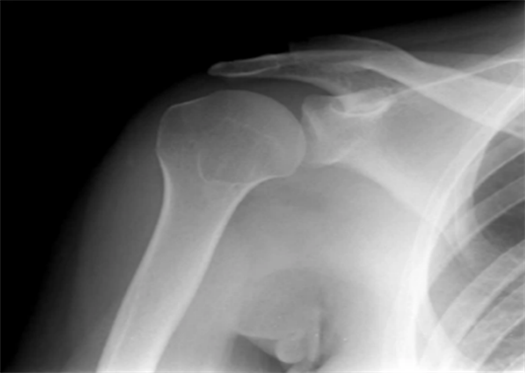

29岁的阿唐(化名),最近4个月一直被一个奇怪的情况困扰着,他的右胳膊会毫无征兆地突然僵住、动弹不得,但人却是完全清醒的。第一次发作是在逛街时,阿唐如往常一样推着自行车走在路边,突然感到右边胳膊控制不了,家人帮忙一看,发现他的右臂不自然地下垂,动弹不得,送到医院后,医生诊断是肩关节脱臼。原以为是推车时劲没使对,复位就没事了,谁知噩梦才刚开始。

此后,阿唐的右臂像被反复“点了穴”一样发作,频频脱臼,甚至在有时候早晨一睡醒,就发现自己肩膀又脱臼了。反反复复的脱臼、永无止境的复位,让阿唐的右肩越来越脆弱,甚至出现了韧带撕裂的征象,阿唐求助医生,希望能通过做手术把韧带修复好,能结束他习惯性脱臼的痛苦,然而医生却无奈地摇头拒绝了他,找不到导致阿唐脱臼的真凶,光做手术是治标不治本的。但没有摔倒,没有剧烈运动,脱臼为何频频发生?这让他和家人都陷入了困惑和焦虑。饱受反复脱臼折磨的阿唐抱着胳膊来到了广东三九脑科医院神经内三科(癫痫内科)。

原来,他大脑中控制右臂运动的区域,会突然发生短暂的、异常的强烈电活动。这种电信号“命令”手臂肌肉强烈、持续地收缩(僵硬),这种不自主的巨大力量,生生将肩关节从关节囊里“拽”了出来,导致了脱臼。发作后,肌肉放松,但关节已经不在原位。

2.不明原因的反复关节脱臼:特别是在没有外伤、没有大幅度动作的情况下反复发生(如肩关节、下颌关节)。这可能是肌肉在癫痫发作时剧烈不自主收缩导致的。